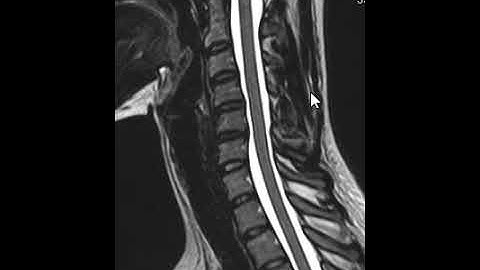

How to Read Your Spine MRI (Pinched Nerves, Cord Compression)